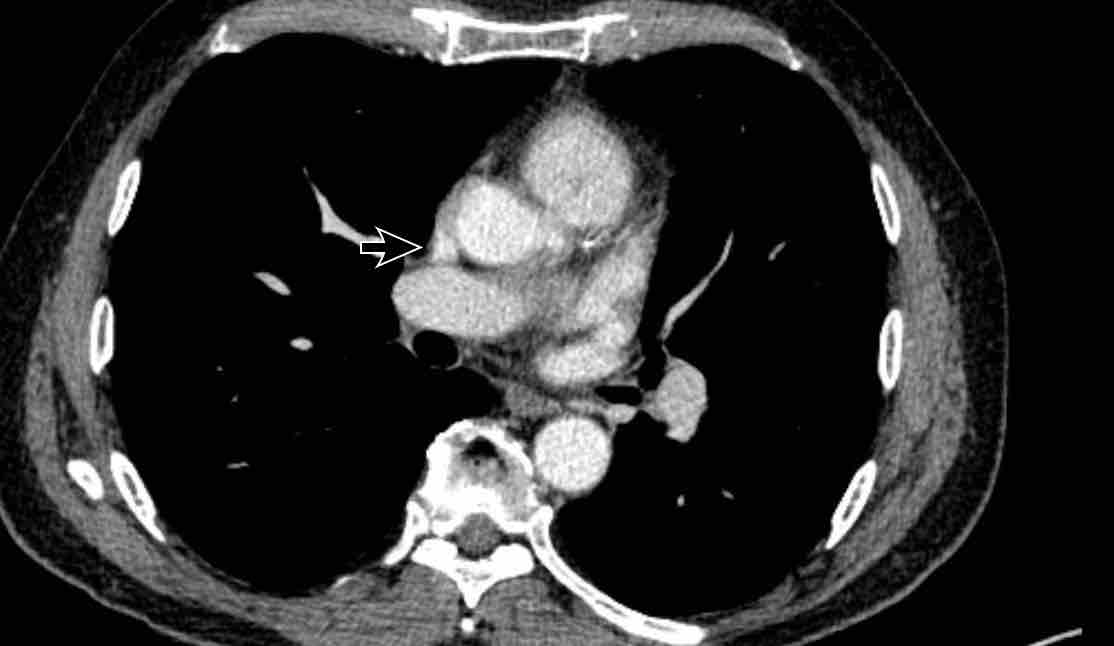

Trong PAPVR, thùy trên trái thường dẫn lưu vào tĩnh mạch tay đầu trái. Bất thường phổ biến tiếp theo là thùy trên phải dẫn lưu vào tĩnh mạch chủ trên.

PAPVR bên phải có mối liên quan chặt chẽ với thông liên nhĩ thể xoang tĩnh mạch (khoảng 40%), đây là một dạng thông liên nhĩ tại vị trí tiếp nối cavo-nhĩ. Do đó, cần kiểm tra sự hiện diện của dạng thông liên nhĩ này khi phát hiện PAPVR bên phải.

Hình ảnh

Bệnh nhân này được lên kế hoạch cắt thùy trên phải do ung thư phổi và bất thường mạch máu này ban đầu đã bị bỏ sót trên hình ảnh CT.

Những hệ quả trong phẫu thuật của bất thường như vậy nhấn mạnh tầm quan trọng của việc không bỏ sót các biến thể này.